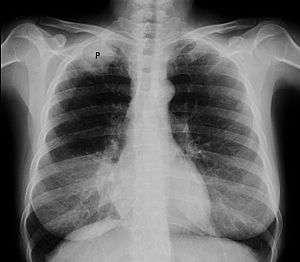

| Chest radiograph showing a Pancoast tumor (labeled as P, non-small cell lung carcinoma, right lung), from a 47-year-old female smoker. | |

A Pancoast tumor, also called a pulmonary sulcus tumor or superior sulcus tumor, is a tumor of the pulmonary apex. It is a type of lung cancer defined primarily by its location situated at the top end of either the right or left lung. It typically spreads to nearby tissues such as the ribs and vertebrae. Most Pancoast tumors are non-small cell cancers.